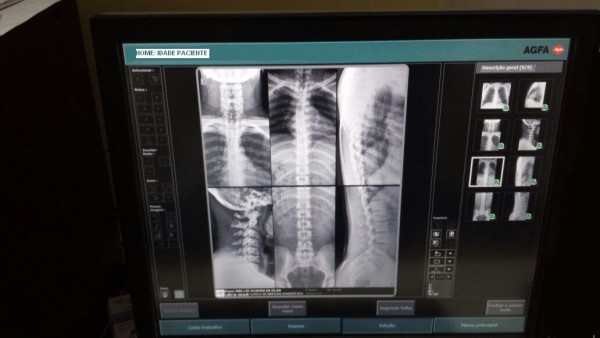

Na administração da ASTIR aplicamos a terceirização na área de “RADIOLOGIA”, desprendendo de serviços burocráticos e técnicos onde com uma só ação, a terceirização, nos beneficiamos com serviços de profissionais 02 (dois) médicos radiologistas, aumento de servidores para atendimento aos associados e dependentes, serviços de “laudos”, e equipamentos modernos na realização dos procedimentos.

Anexo: Imagens Aparelhos modernos (fugura 01 e 02) e Ofício em resposta da Ultra-Med. Figura (03).